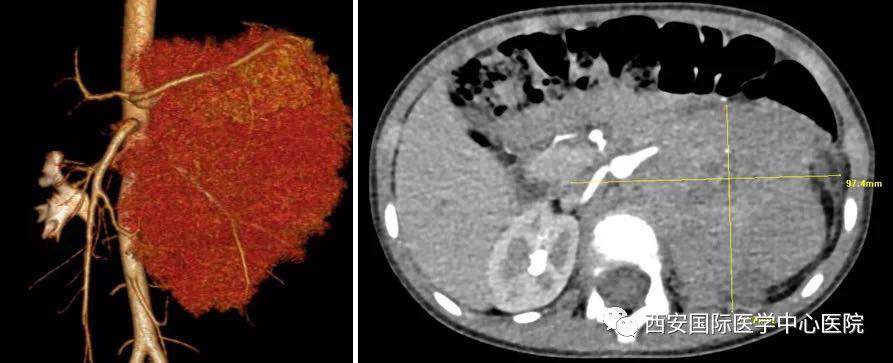

入院后,楊增悅主任仔細詢問病史、查閱影像學(xué)資料,第一時間為依依安排骨髓穿刺活檢,最終確診為:腹膜后神經(jīng)母細胞瘤(Ⅳ期/L2)。CT顯示腫瘤巨大,侵及腹主動脈、腹腔干、腸系膜上動脈、雙腎動脈、腸系膜下動脈、下腔靜脈、雙腎靜脈、左腎及腎上腺、胰十二指腸、脾臟、結(jié)腸脾曲;腹膜后多發(fā)淋巴結(jié)轉(zhuǎn)移、骨轉(zhuǎn)移。骨穿病檢示:神經(jīng)母細胞瘤骨髓轉(zhuǎn)移,腫瘤細胞占90.5%。經(jīng)過科室團隊討論后決定,先行新輔助化療后再進行手術(shù)治療。